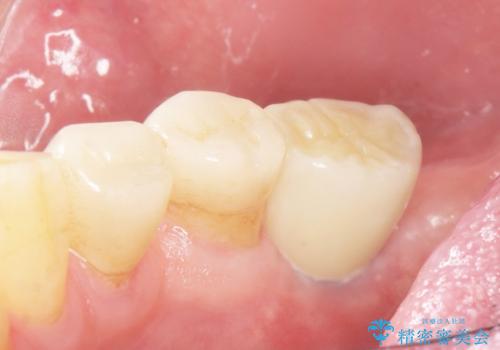

- 奥歯の違和感を主訴に来院された患者様です。

精査したところ、右下の奥歯は大きなう蝕により保存不可能な状態でした。

患者様のご希望により、抜歯後インプラント治療を行いました。